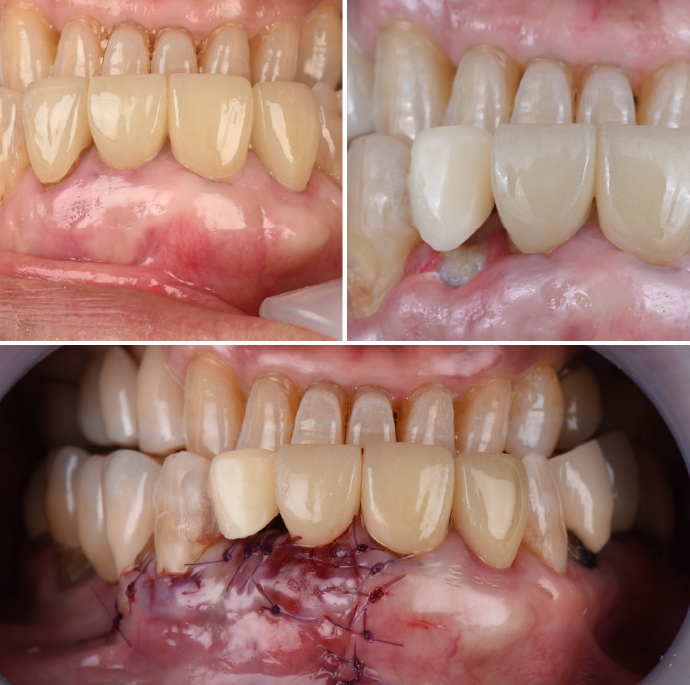

SRPでも改善が見られない重度の症例では、歯肉を切開してポケット奥深くまで歯石などを除去する外科的処置を行います。

歯周病によって破壊された歯周組織(歯肉・歯槽骨など)を、骨補填材や薬剤を用いて再生を促す治療です。適応症例・術後管理が重要です。

| 治療内容 | 上段 根面被服術(歯茎を上げる手術) |

| 治療費 | 総額 88000円〜 |

| 治療回数 | 1回 |

| リスク | 術部の発赤、腫脹、疼痛、部分的なネクローシス |

| 治療内容 | 下段 歯周外科(再生療法) |